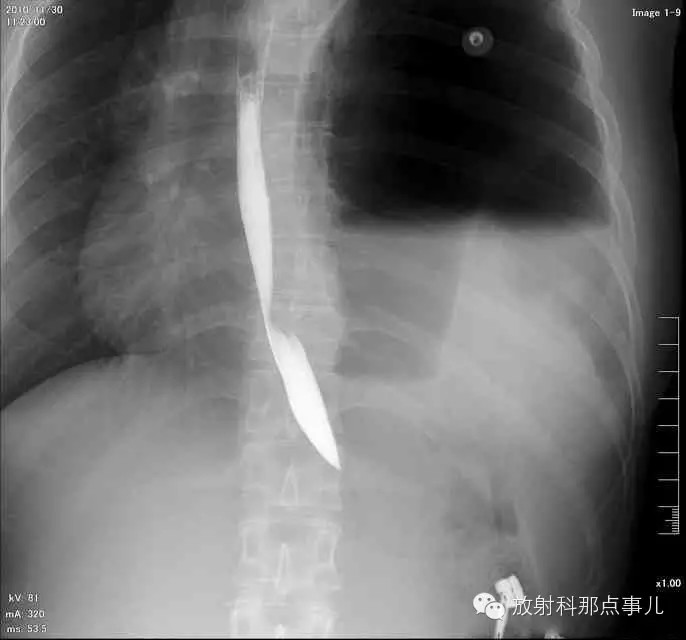

门诊腹部透视发现左侧胸腔巨大气液平面,为排除膈疝口服钡剂,但造影剂未见进入胃内。嘱住院,外科给予胃肠减压、补液等处理常规处理(未引流出明显气、液体)。5个半小时后再次检查,见少量造影剂进入消化道;为进一步了解情况,予泛影葡胺分别经胃管推注及口服,但均未进入胃内。当天进行外科急诊手术。

大部分胃、脾及横结肠均经过胸肋三角疝入左侧胸腔内,并见疝环形成。

考虑该患者因生产过程中腹压急剧升高,导致腹内脏器经膈肌缺损或薄弱部位进入胸腔内。